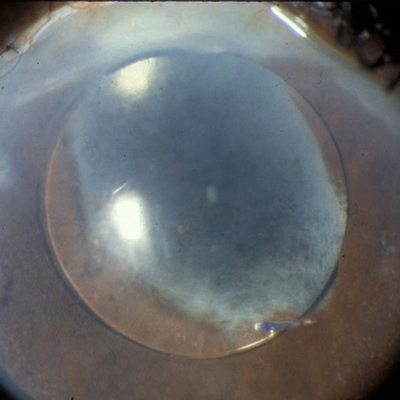

Corneal edema after cataract surgery is expected to an extent, but as postop recovery stretches to 1 month or beyond, surgeons begin to treat the situation differently. Three surgeons discussed preop contributors, prevention, diagnosis, and treatment of prolonged corneal edema.